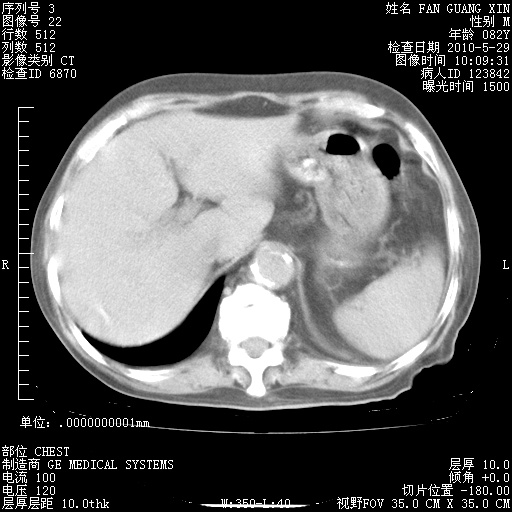

再治疗10天后的肺部CT 纵膈窗

阅读此次胸部CT,肺间质渗出性改变较入院时有吸收。目前从体温、白细胞、中性分叶明显增高,肯定存在细菌感染(发生医院感染哦,若无消化道及泌尿系统等感染的依据,肺部感染可能大)。若你院头孢哌酮舒巴坦钠耐药率较高,同意你的方案,若48小时体温仍高,可考虑使用碳青霉稀类抗菌药物,同时可予超声雾化、注意滴数时加大液体量。白蛋白33.30g/L较低哦,需加强营养等支持治疗。